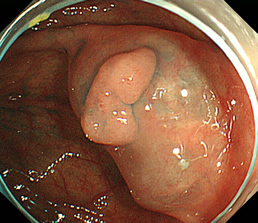

見つかったポリープ

ポリープに色素を吹きかけた状態

粘膜下層に生理食塩水を注入し、盛り上げた状態

高周波電流で粘膜下切除を行った状態

切除後クリップにて止血胃瘻造設術